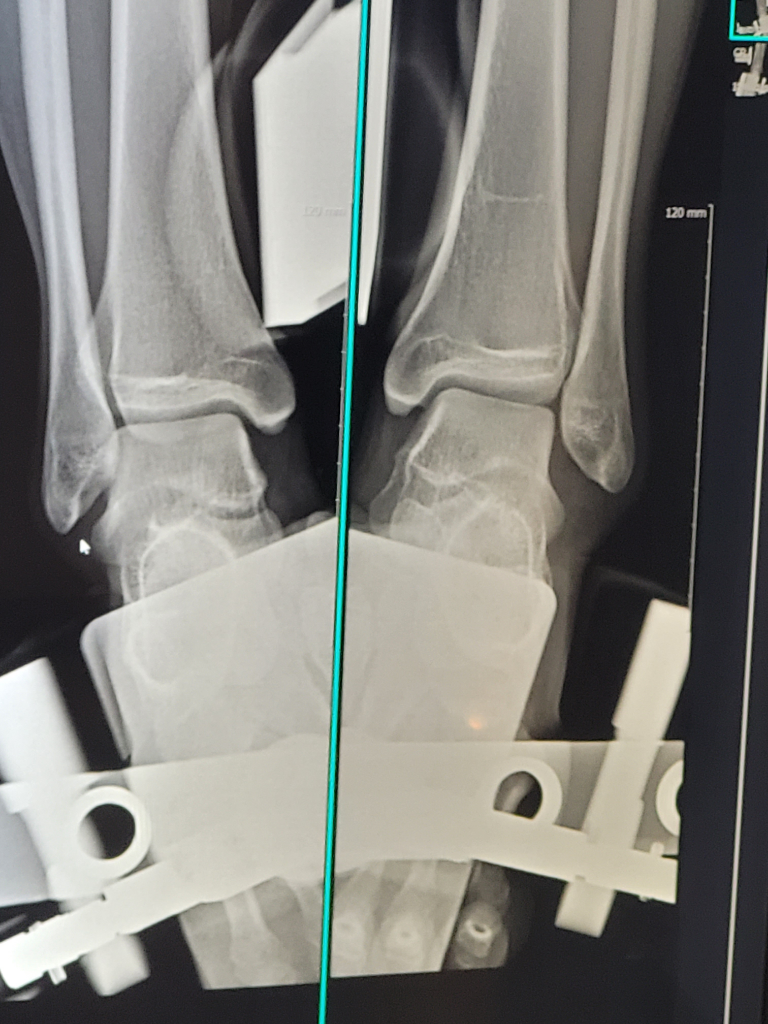

발목인대 파열 스트레스뷰 어디가 벌어진건가요?

오른쪽 사진이 제 왼쪽 발목입니다. 사고 이후 6일차에 촬영했습니다. 전거비 완파 종비 거의 완파 입니다. 저 벌어진 부분이 어디랑 어디가 벌어진거라고 하면 되는지 궁금합니다.

스트레스 뷰에서 보이는 벌어짐은 거골과 중골, 비골 사이 관절 간격이 넓어진 것입니다. 이는 주로 전거비인대와 종비인대가 손상되었을 때 나타납니다. 즉 거골이 외측으로 밀리면서 거골~비골 간격이 정상보다 벌어진 모습으로 해석할 수 있습니다.

쉽게 말해 발목 외측 인대가 끊어져서 거골이 비골 쪽으로 벌어진 것 이라고 설명하면 됩니다!